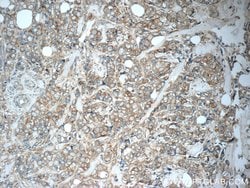

This antibody is specifically against KRT7.

Cytokeratin 7 blocks interferon-dependent interphase and stimulates DNA synthesis in cells. Involved in the translational regulation of the human papillomavirus type 16 E7 mRNA (HPV16 E7).Specifications

| Immunocytochemistry, Immunofluorescence, Immunohistochemistry (Paraffin), Immunoprecipitation, Western Blot | |